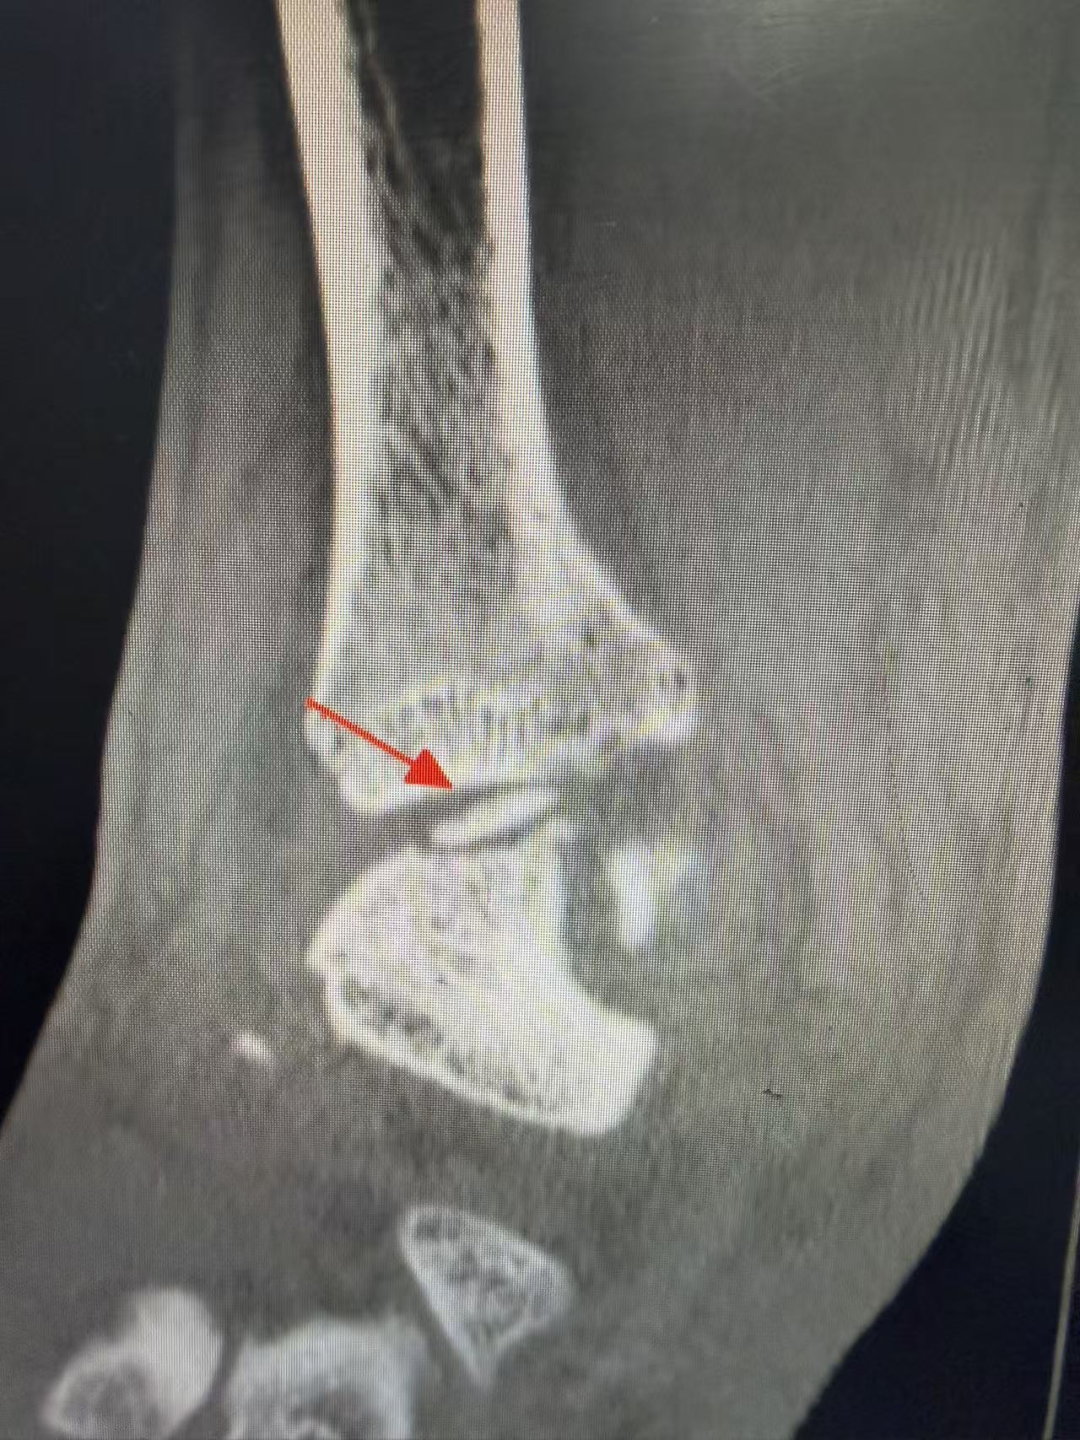

踝关节正位片

术前影像学检查